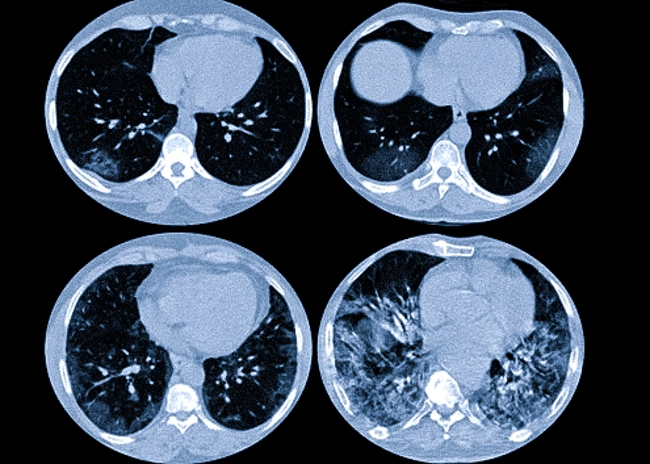

Компьютерная томография

Компьютерная томография (КТ) даёт более детальное изображение легких и может выявить заболевания‚ которые не были обнаружены на рентгенограмме. Это обследование особенно важно для людей с высоким риском рака легких.